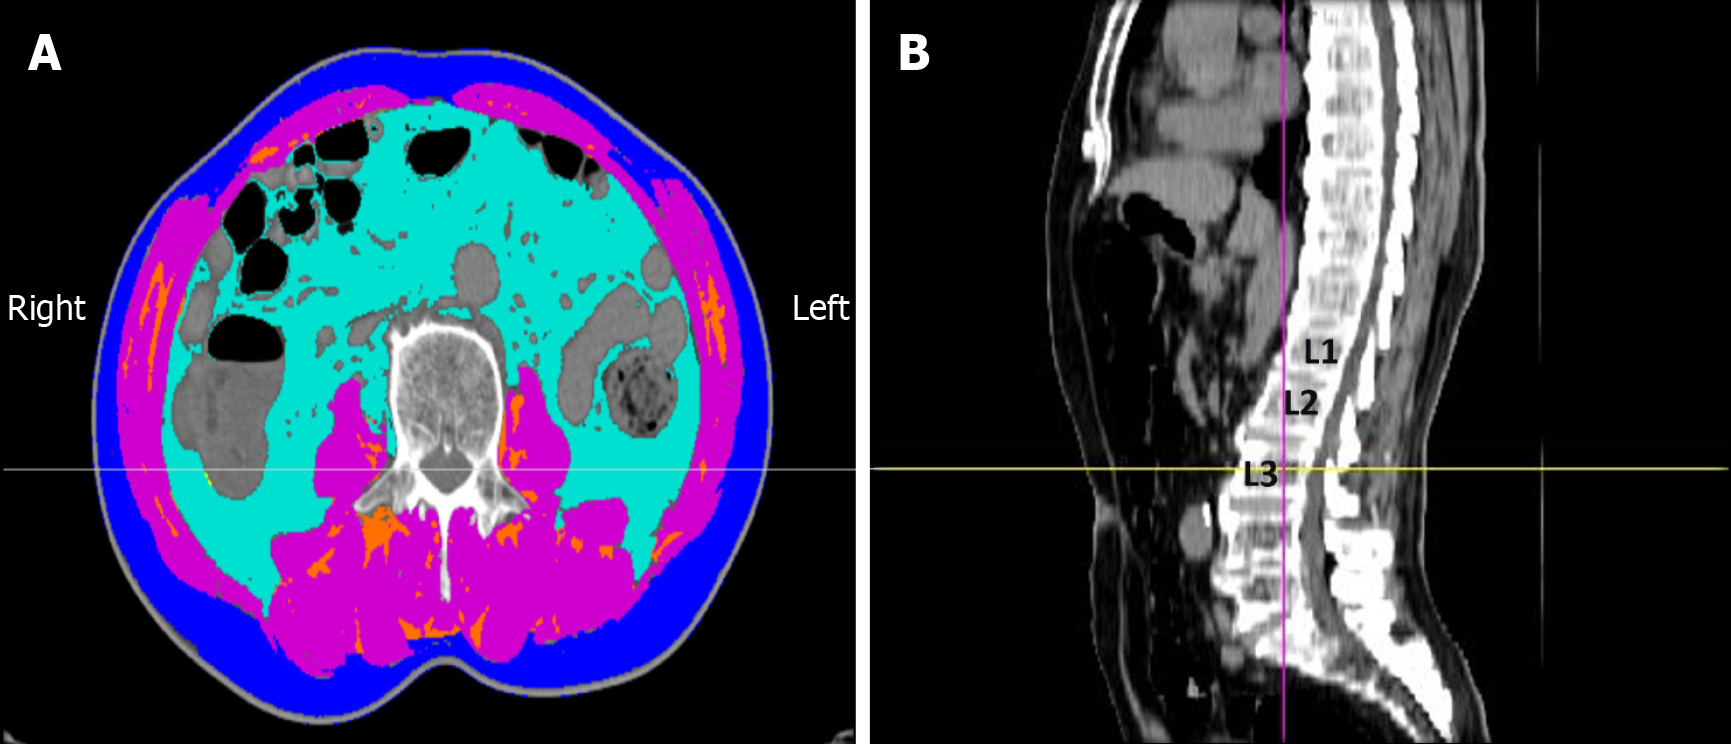

Figure 1 Assessment of body composition by computed tomography at the third lumbar vertebra (L3) level.

A: Axial computed tomography (CT) image showing the segmentation of different tissue compartments: Skeletal muscle area (SMA) [pink, -29 to +150 Hounsfield units (HU)], visceral adipose tissue area (light blue, -150 to -50 HU), subcutaneous adipose tissue area (dark blue, -190 to -30 HU), and intermuscular adipose tissue area (orange, -190 to -30 HU); B: Sagittal CT image indicating the L3 level for axial analysis. The skeletal muscle index was calculated as the SMA divided by the square of the patient’s height (SMA/height2).